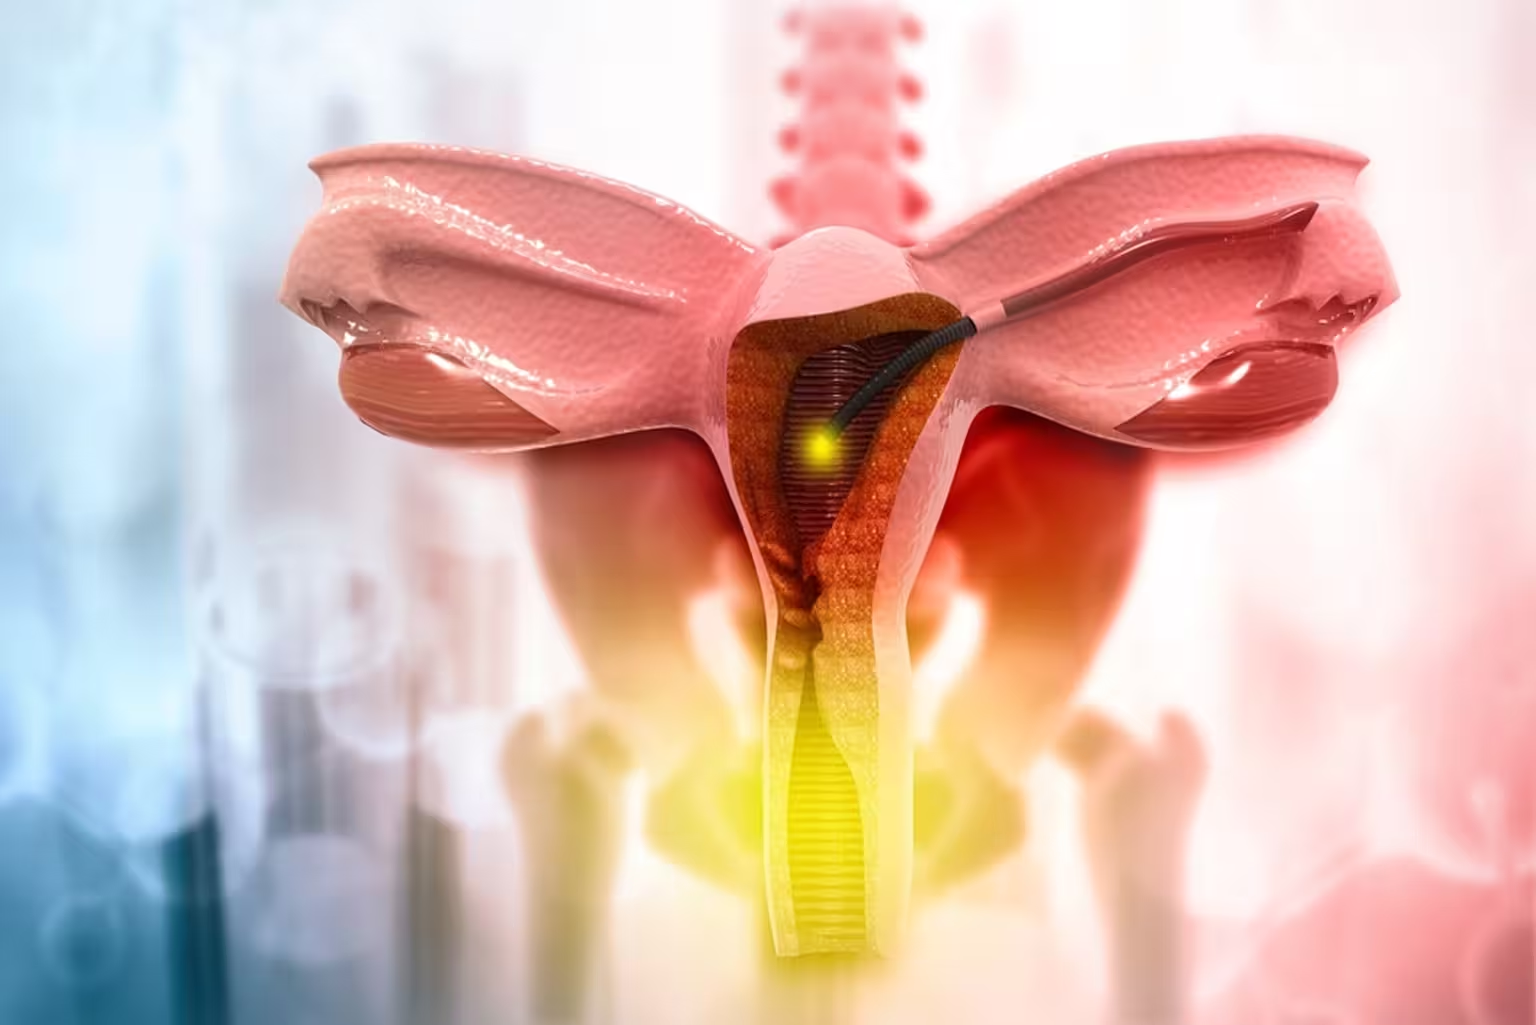

Cosmetic Gynae Care and surgery By Dr Deepali Luthra Jalandhar - Cosmetic Gynaecological Surgery, or Aesthetic Gynaecology, focuses on enhancing the appearance, function, and comfort of the female genitalia through surgical and non-surgical procedures.

Common surgeries include labiaplasty (reshaping the labia), vaginoplasty (vaginal tightening), and hymenoplasty (hymen reconstruction). Non-surgical options like laser vaginal rejuvenation and radiofrequency therapy improve tightness and lubrication, while G-spot augmentation and O-Shot enhance sexual sensitivity.

Women seek these procedures for various reasons, including post-childbirth restoration, aging effects, discomfort during activities, or aesthetic preferences. While mostly elective, some surgeries also address functional concerns like discomfort or reduced sensation.

Performed by qualified specialists, these procedures can boost confidence and quality of life. However, informed decision-making and understanding potential risks are essential before undergoing treatment.

The Sabrina Laser is an innovative, non-ablative, and non-invasive laser therapy designed to enhance vaginal and pelvic floor health. Utilizing a solid-state hybrid triad laser with wavelengths of 1470 nm and 980 nm, it effectively stimulates collagen production and remodeling within the vaginal mucosa. This process addresses various conditions such as pelvic organ prolapse, stress urinary incontinence, vaginal laxity, and genitourinary syndrome of menopause. The treatment is gentle, typically painless, and does not require anesthesia, allowing patients to resume their daily activities immediately. Notably, the Sabrina Laser is available at Chawla Nursing Home and Maternity Hospital in Jalandhar, Punjab, India, offering advanced care for women's health concerns

Labiaplasty is a surgical procedure that involves the reduction or reshaping of the labia minora (the inner lips of the vagina) to enhance both appearance and comfort.

Monsplasty is a surgical procedure designed to reduce excess fat and skin in the mons pubis area, enhancing both comfort and aesthetics. If you are considering this procedure.

Perineoplasty is a surgical procedure designed to restore and tighten the perineal area, often affected by childbirth, aging, or trauma. If you are considering this procedure

Clitoral hood reduction is a specialized surgical procedure designed to enhance comfort, aesthetics, and sexual wellness by reducing excess tissue around the clitoral hood.

Cosmetic Gynaecological Surgery is chosen by women for both aesthetic and functional reasons, helping enhance confidence, comfort, and overall well-being.

Many opt for procedures like labiaplasty, vaginoplasty, and laser vaginal rejuvenation to restore the genital area after childbirth, aging, or weight loss. These treatments can improve sexual satisfaction, reduce discomfort during physical activities, and enhance vaginal tightness and lubrication.

For some, cosmetic gynaecology addresses self-esteem concerns, allowing them to feel more comfortable in intimate relationships. Others seek relief from irritation, chafing, or asymmetry, which can affect daily life and exercise.

Additionally, cultural or personal preferences may influence choices like hymenoplasty or monsplasty.

Cosmetic Gynaecology includes surgical and non-surgical procedures designed to enhance the appearance, function, and comfort of the female genital area. Common procedures include labiaplasty, vaginoplasty, hymenoplasty, laser vaginal rejuvenation, and more.

Any woman experiencing discomfort, aesthetic concerns, or reduced vaginal tightness due to aging, childbirth, or other factors can consider these treatments. A consultation with a specialist can help determine the best option.